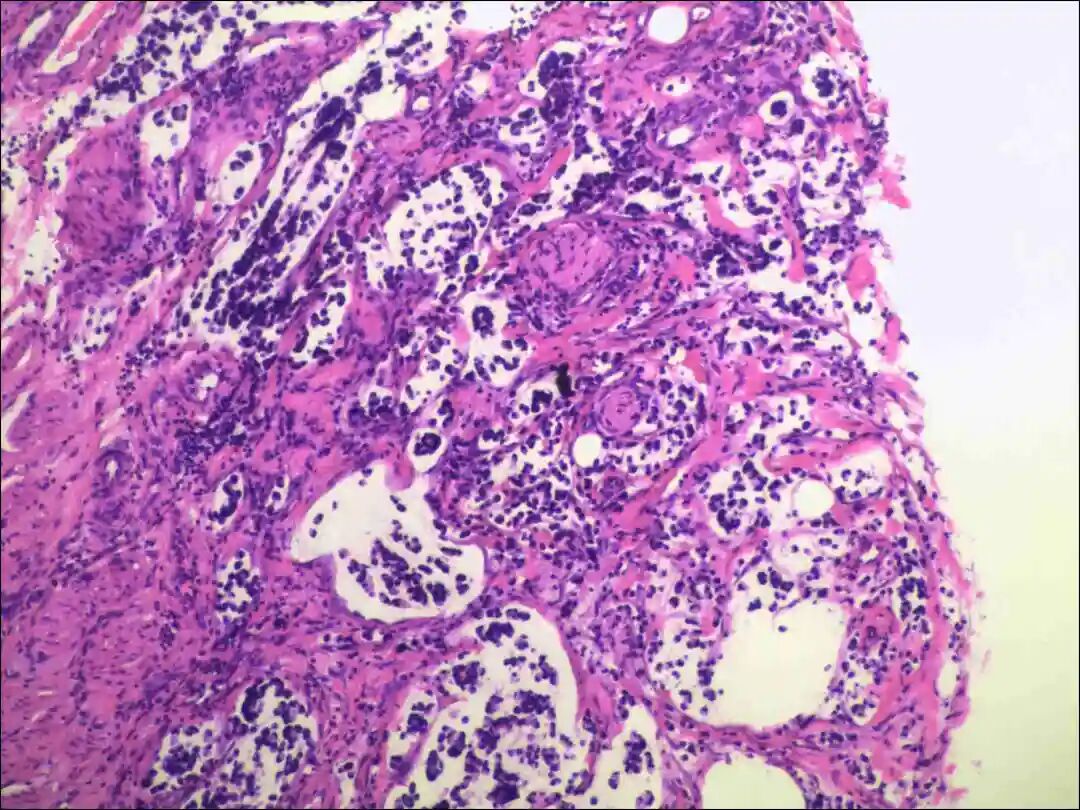

2.黏液腺癌基础特征:肿瘤细胞分泌大量细胞外黏液形成“黏液湖”,癌细胞漂浮其中或呈巢状、腺样排列,细胞核多为低 - 中级别,核分裂象低。

1. 形态学诊断:肿瘤组织含大量细胞外黏液,黏液成分占比通常>90%(单纯型),癌细胞呈小簇状、巢状漂浮于黏液湖中,B型乳腺黏液癌等可表现为细胞丰富伴神经内分泌形态(如胞质颗粒状)。